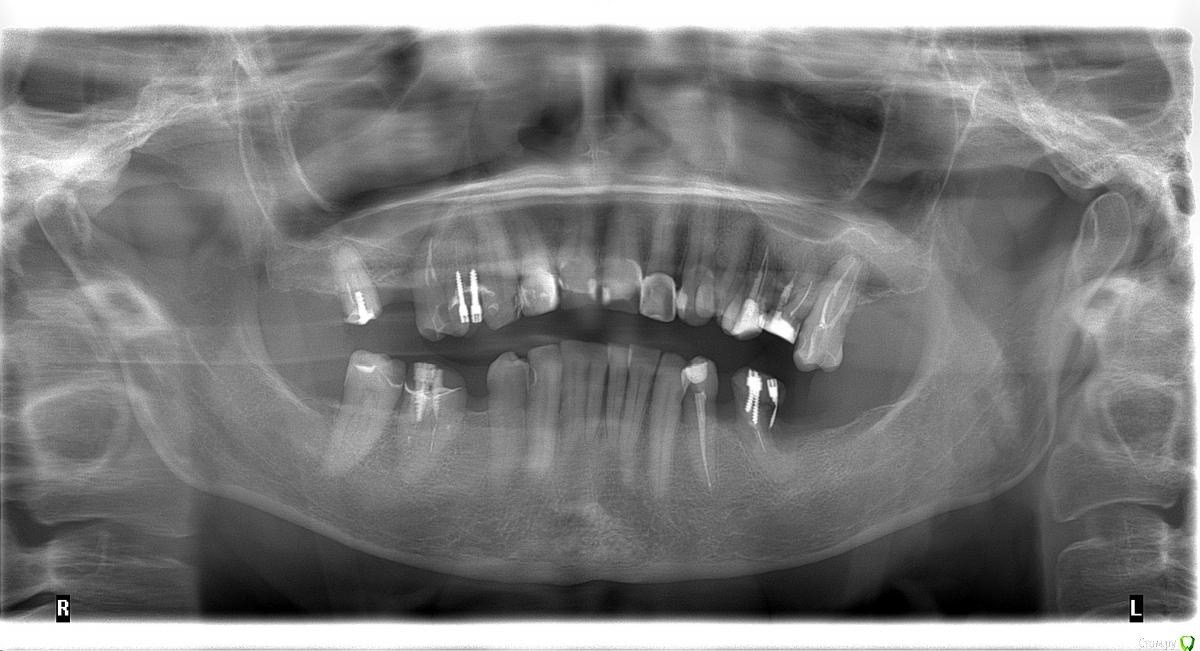

dr.Dre Опубликовано 22 июня, 2017 Поделиться Опубликовано 22 июня, 2017 Добрый день уважанмые коллеги,пациентка 58 лет .Помогите составить план лечения,имплантацию не потянет .Нужно ли здесь поднимать прикус? Ссылка на комментарий

dr.Dre Опубликовано 24 июня, 2017 Автор Поделиться Опубликовано 24 июня, 2017 Что хочет пациент?Мк ,фронт безметал Ссылка на комментарий